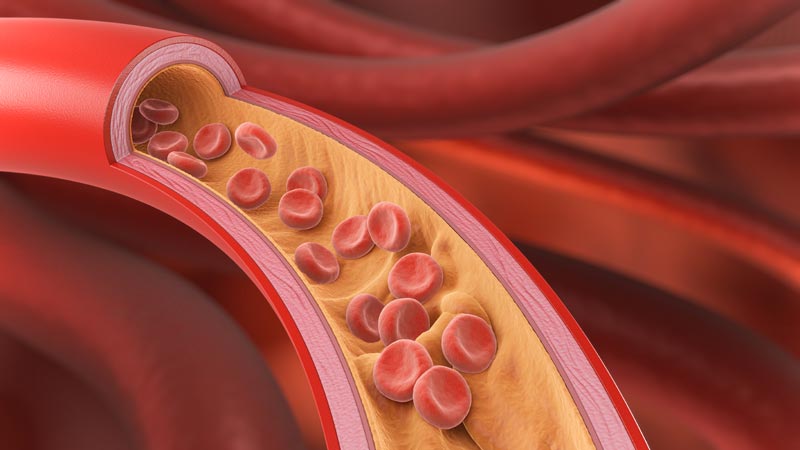

Gefäßerkrankungen sind wie der unhöfliche Gast auf einer Party, der sich reinschleicht, den Kühlschrank leert und erst bemerkt wird, wenn das Buffet ruiniert ist. Arteriosklerose, Aneurysmen oder venöse Probleme entstehen über Jahrzehnte. Das Gemeine daran? Sie bleiben lange vollkommen symptomlos. Man fühlt sich fit, geht vielleicht sogar regelmäßig spazieren, und währenddessen arbeiten sich die Ablagerungen fleißig durch das Leitungssystem Ihres Körpers.

Wir wissen es alle, aber wir ignorieren es gerne: Rauchen, Bluthochdruck und ein erhöhtes LDL-Cholesterin sind die besten Freunde des Gefäßchirurgen – zumindest sichern sie dessen Arbeitsplatz. Wer seine Arterien wie ein altes Abflussrohr mit Fett und Nikotin zusetzt, darf sich nicht wundern, wenn der Druck irgendwann zu hoch wird.

Eine völlig schmerzfreie Untersuchung, die Leben rettet. Ein Aneurysma (eine Aussackung der Schlagader) merkt man nicht. Man spürt es nicht. Es tut nicht weh. Bis es reißt – und dann ist meistens Ende im Gelände. - Früherkennung